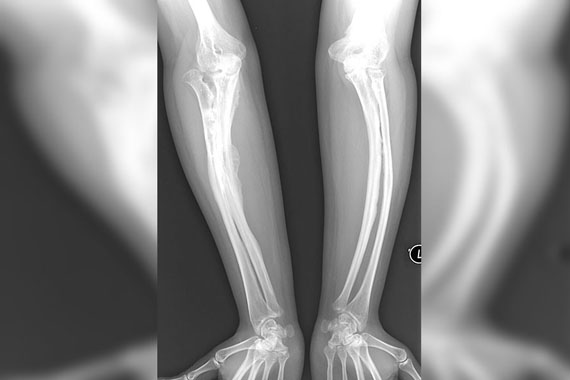

İsminden de anlaşıldığı gibi kemiklerin adeta cam gibi kırılgan olduğu bir sağlık sorunu olan cam kemik hastalığının tedavisi için yeni bir umut doğdu. Türk bilim insanlarının yaptığı bir araştırmada cam kemik hastalığına neden olan bir gen keşfedildi. Bu gen sayesinde yeni bir ilaç üretilmesi mümkün olabilecek.

Kemikler adeta cam gibi kırılgan oluyor. Bu hastalıktan muzdarip kişilerin hayat kalitesi işkenceye dönüşebiliyor. 1990’lı yıllarda başlayan DNA çalışmalarının ardından dünya artık genetik tedavilere yöneldi. Dünyada 10 binde bir kişide görülen cam kemik hastalığı için de birçok çalışma yapıldı.

Cerrahpaşa Tıp Fakültesi Çocuk Genetik Bilim Dalı Başkanı Profesör Doktor Beyhan Tüysüz ve ekibi özel bir çalışma yaptı. Yaptıkları çalışmayla cam kemik hastalığına neden olan yeni bir tipi ve yeni bir geni keşfetti. Yapılan çalışma, cam kemik hastaları için tedavi umudu oldu.

Araştırma önce genişletildi, ardından yayımlandı. Devrim niteliği taşıyan gen keşfi öncelikle "cam kemik" hastalığı tespitinde kullanılacak. İstanbul Üniversitesi Cerrahpaşa Fakültesi laboratuvarında yapılan bu araştırmanın genişletilerek cam kemik hastaları için umut olması bekleniyor.